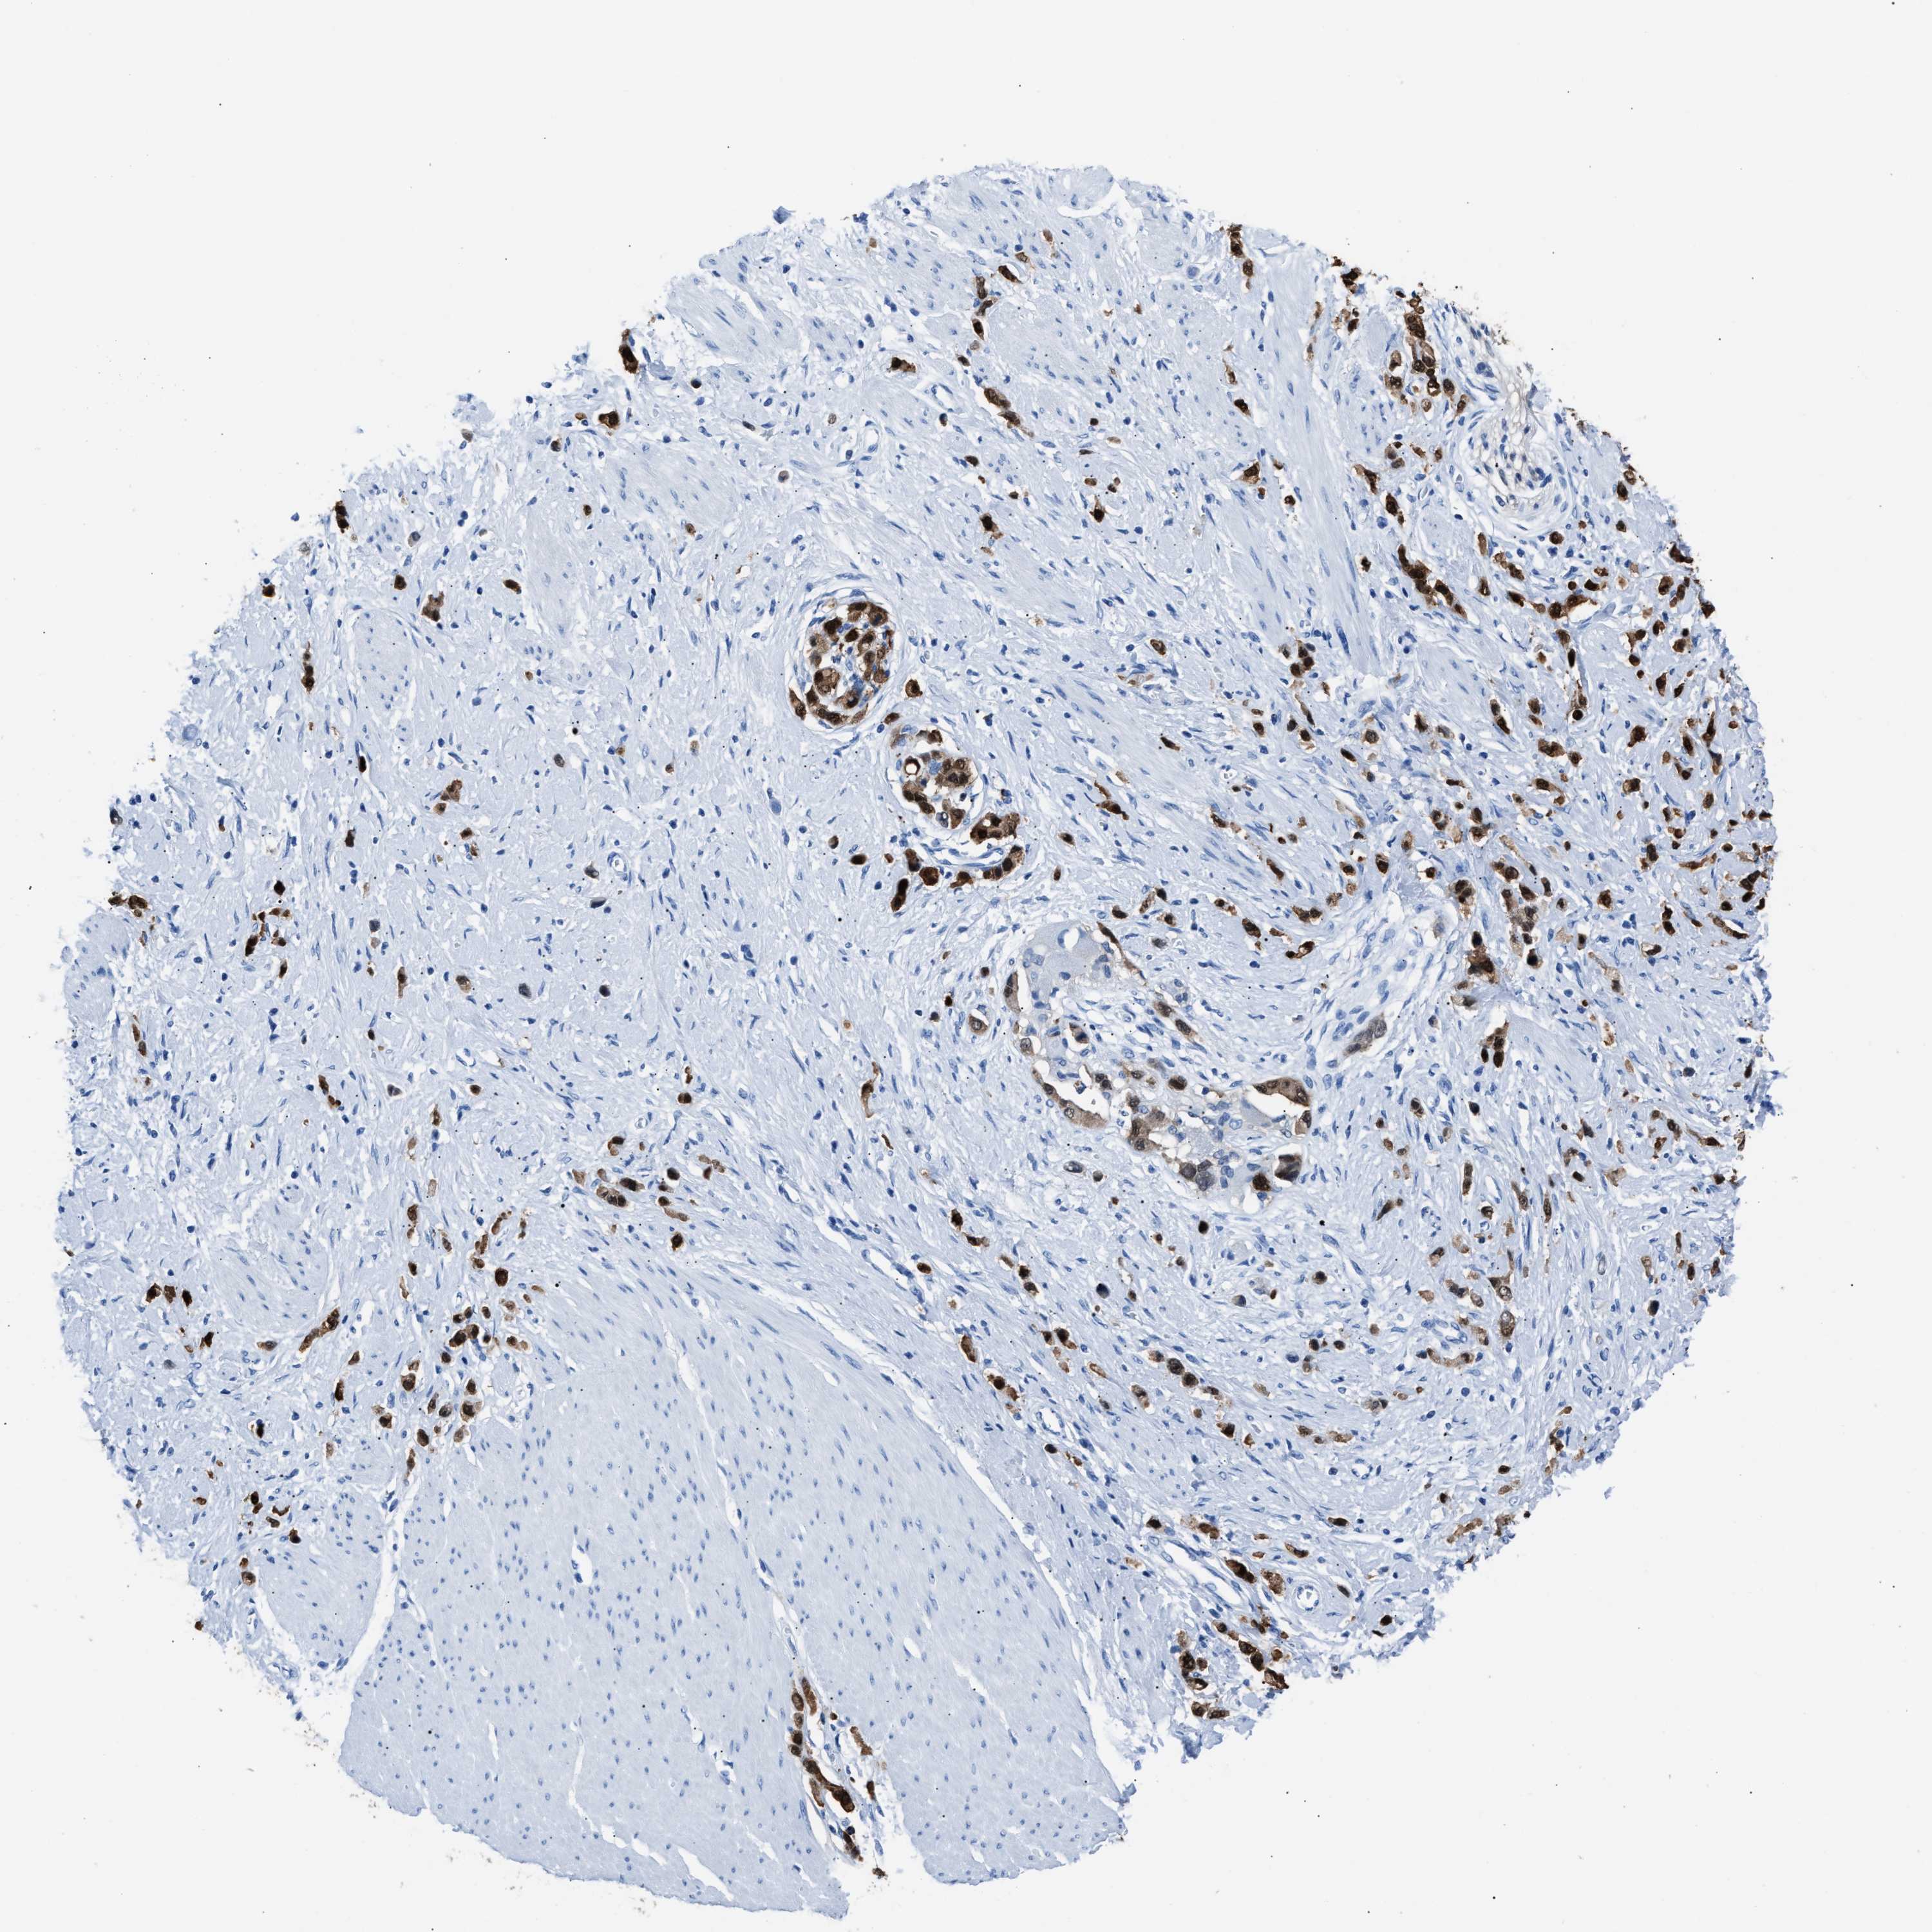

STOMACH CANCER - Protein expressioni

A mouse-over function shows sample information and annotation data. Click on an image to view it in a full screen mode. Samples can be filtered based on level of antibody staining by selecting one or several of the following categories: high, medium, low and not detected. The assay and annotation is described here.

Note that samples used for immunohistochemistry by the Human Protein Atlas do not correspond to samples in the TCGA dataset.

Antibody stainingi

Antibody staining in the annotated cell types in the current human tissue is reported as not detected, low, medium, or high, based on conventional immunohistochemistry profiling in selected tissues. This score is based on the combination of the staining intensity and fraction of stained cells.

Each image is clickable and will lead to virtual microscopy that enables deeper exploration of all samples and also displays staining intensity scores, fraction scores and subcellular localization as well as patient and tissue information for each sample.

Antibody HPA019502

Staining

High

Medium

Low

Not detected

Intensity

Strong

Moderate

Weak

Negative

Quantity

>75%

75%-25%

<25%

None

Location

Nuclear

Cytoplasmic/membranous

Cytoplasmic/membranous,nuclear

Adenocarcinoma, NOS